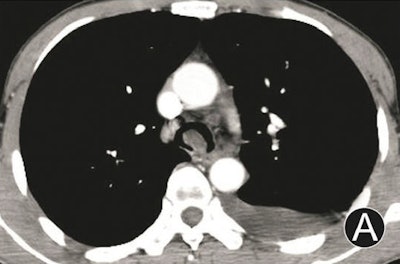

- Intraluminal and extraluminal tumors: These manifest as infiltrated growth along thickened walls, with invasion extraluminally, and masses both intraluminally and extraluminally.

Tumors with dominant intraluminal growth have significant luminal stenoses, the group noted. Tumors with evident extraluminal growth may resemble mediastinum tumors. Tumors with apparent intraluminal and extraluminal growth have large masses and are often obstructive.